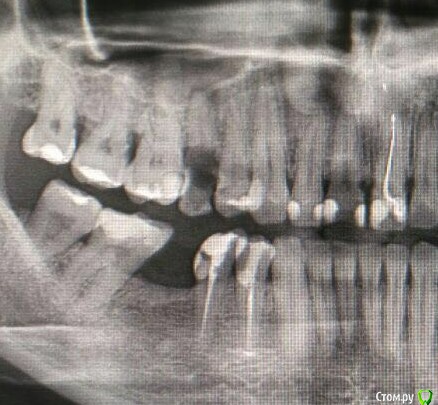

Леголич Опубликовано 2 марта, 2018 Автор Поделиться Опубликовано 2 марта, 2018 Снимок Ссылка на комментарий

Леголич Опубликовано 2 марта, 2018 Поделиться Опубликовано 2 марта, 2018 Доброго времени суток! Ситуация такова, что с 15 зубом надо мне прощаться без вариантов. И мне на выбор предложили 2 пути. 1. Имплантолог: Поставить имплант с синуслифтингом. Доводы: одномоментно убрали, поставили. Воспаление? Кюретаж нам в помощь.2. Ортодонт: ставим брекеты ( в планах по любому это было- ровняю верхние зубы глобально), после удаляем и на лунку зубы сместятся быстро. Доводы: все зубы живые(18,17,16,14,13,11) двигаются легко и никаких имплантов, к тому же он может помешать изменению прикуса.Посоветуйте, как на Ваш взгляд, что лучше? Имплантация или ортодонтия в моем случае? Спасибо! Ссылка на комментарий